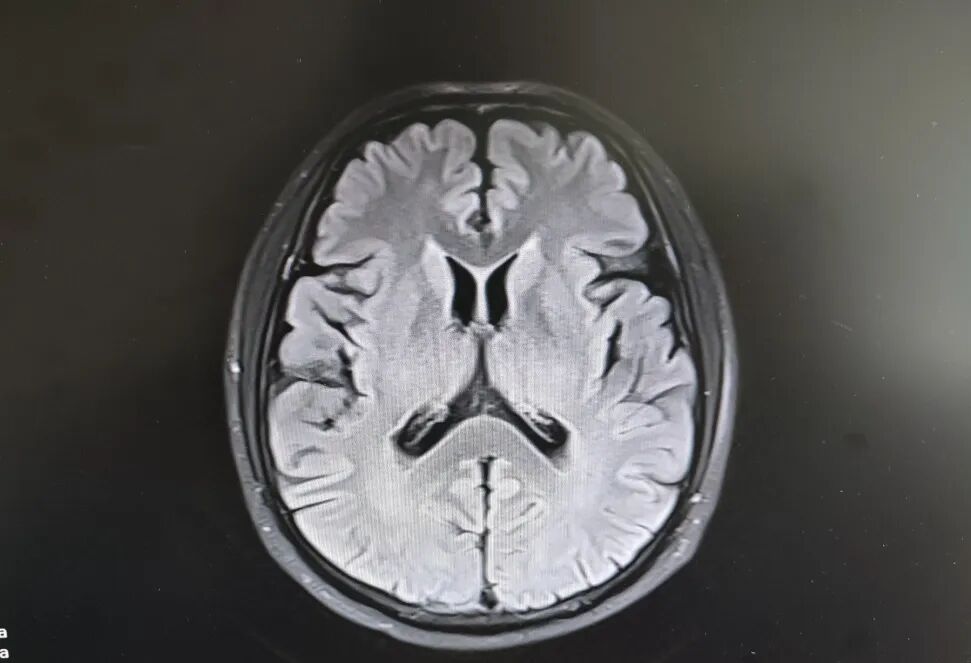

患者頭部磁共振影像